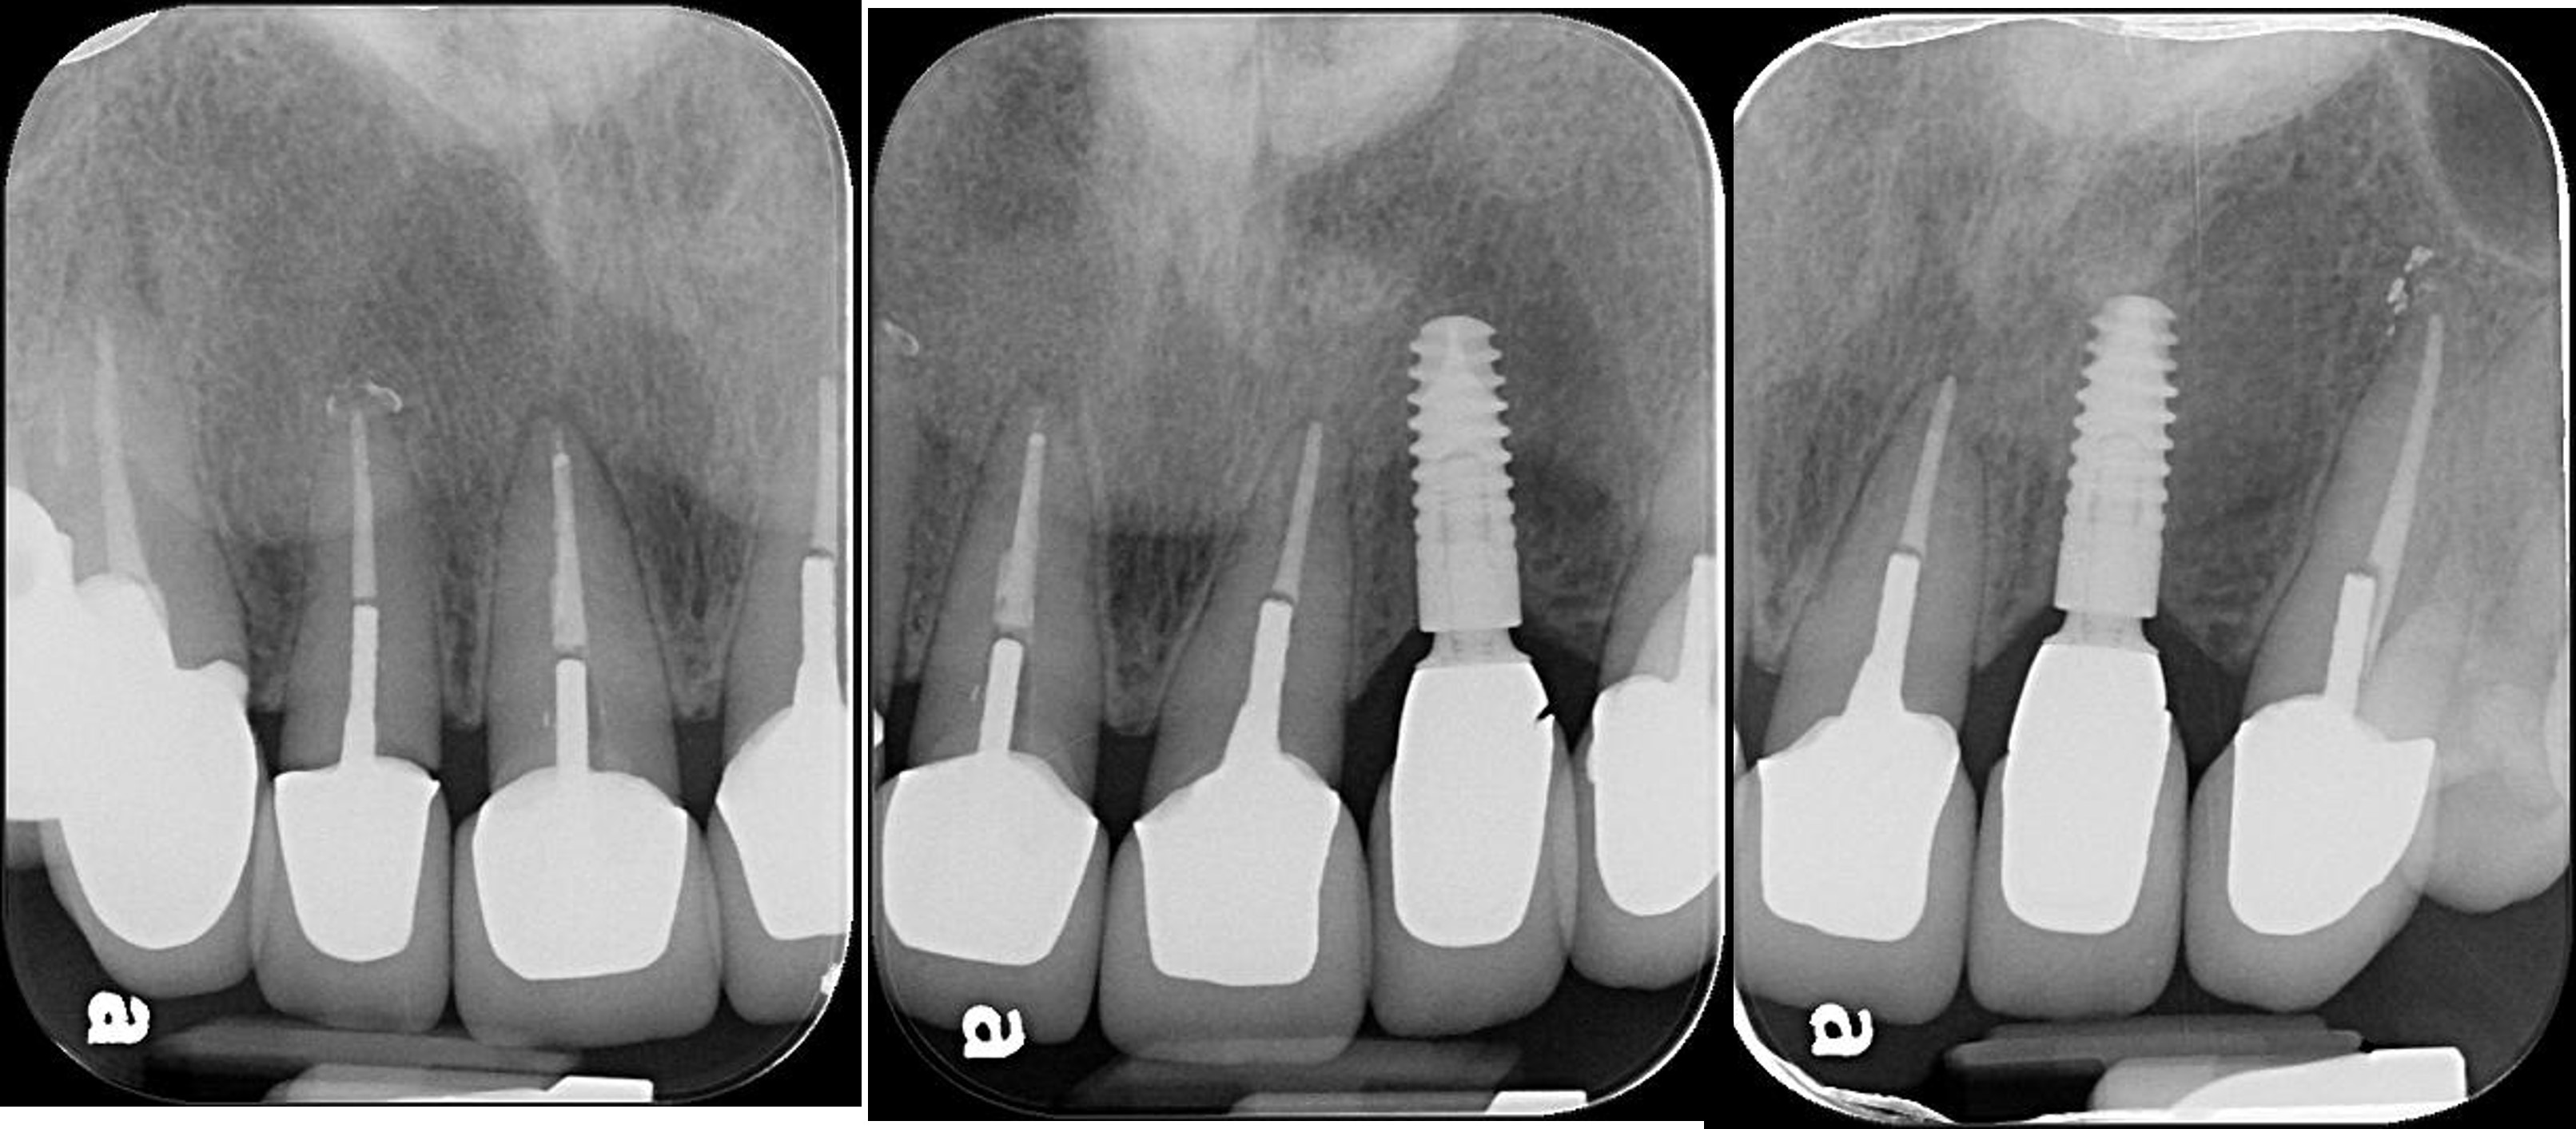

3)立即植牙

拔牙、立即植牙、補骨、補皮

牙齦豐隆度良好